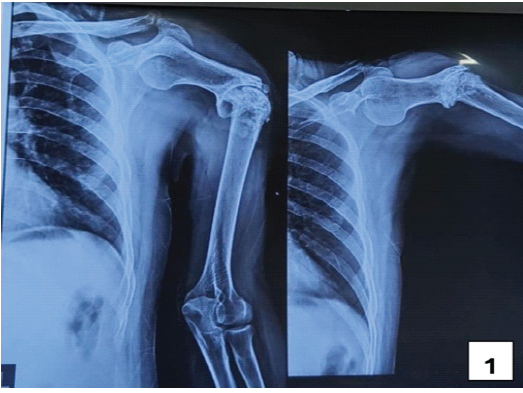

A 60-year-old male presented to our outpatient department with a noticeable deformity in his left arm, which was substantially limiting his daily activities. He had a history of smoking and hypertension. The patient reported a history of a closed fracture of the left humeral shaft 40 years prior, treated conservatively with cast immobilization. Clinical examination demonstrated significant deformity and functional impairment of the left arm. His shoulder range of motion was significantly limited with 30° of flexion, 15° of extension, 30° of abduction, 15° of adduction, 20° of internal rotation, and 15° of external rotation. Elbow flexion was also restricted, ranging from 15° to 70°. The constant shoulder score was 21. X-ray examination confirmed an oligotrophic non-union with pseudoarthrosis at the junction of the proximal and mid-third of the left humeral shaft (Fig. 1). His pre-operative evaluations, including white blood cell count (7500 cells/mm3), C-reactive protein (0.7 mg/dL), and erythrocyte sedimentation rate (15 mm/h), were within normal limits.

Figure 1: Pre-operative X-ray showing oligotrophic nonunion with pseudoarthrosis at the junction of the proximal and mid-third of the left humeral shaft.